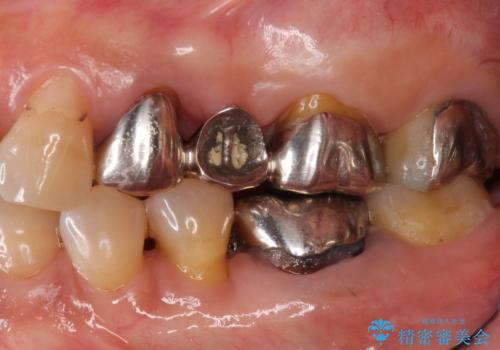

- 20年前に治療した銀歯が壊れ、審美的な修復を希望され来院されました。

銀歯・虫歯を除去し、ジルコニアを咬合再構成を行います。